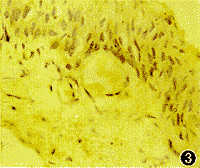

图3 Ⅲ组翼状胬肉上皮细胞、成纤维细胞及血管内皮细胞PCNA表达明显减弱 免疫组化×400